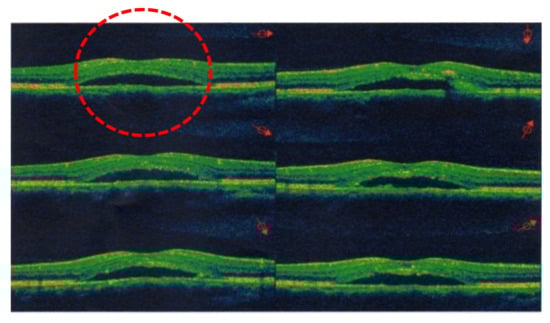

- Tatham, A.; MaCfarlane, A. The use of propranolol to treat central serous choriretinopathy: An evaluation by serial OCT. J. Ocul. Pharmacol. Ther. 2006, 22, 145–149. [Google Scholar] [CrossRef]